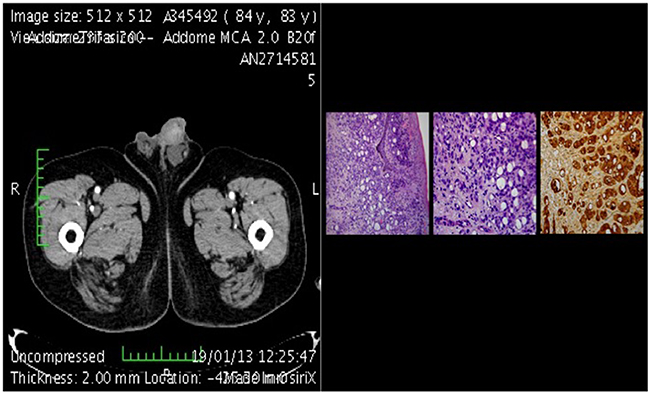

10 patients presented with priapism as the first symptom (5 from urological and 5 from non-urological cancers). Patients with priapism from urological cancer had a median cancer specific survival time of 30 months, patients with priapism from non-urological cancer had a median cancer specific survival time of 15 months (Figure 4).

Figure 4: CT-scan of metastasis plus histological section.